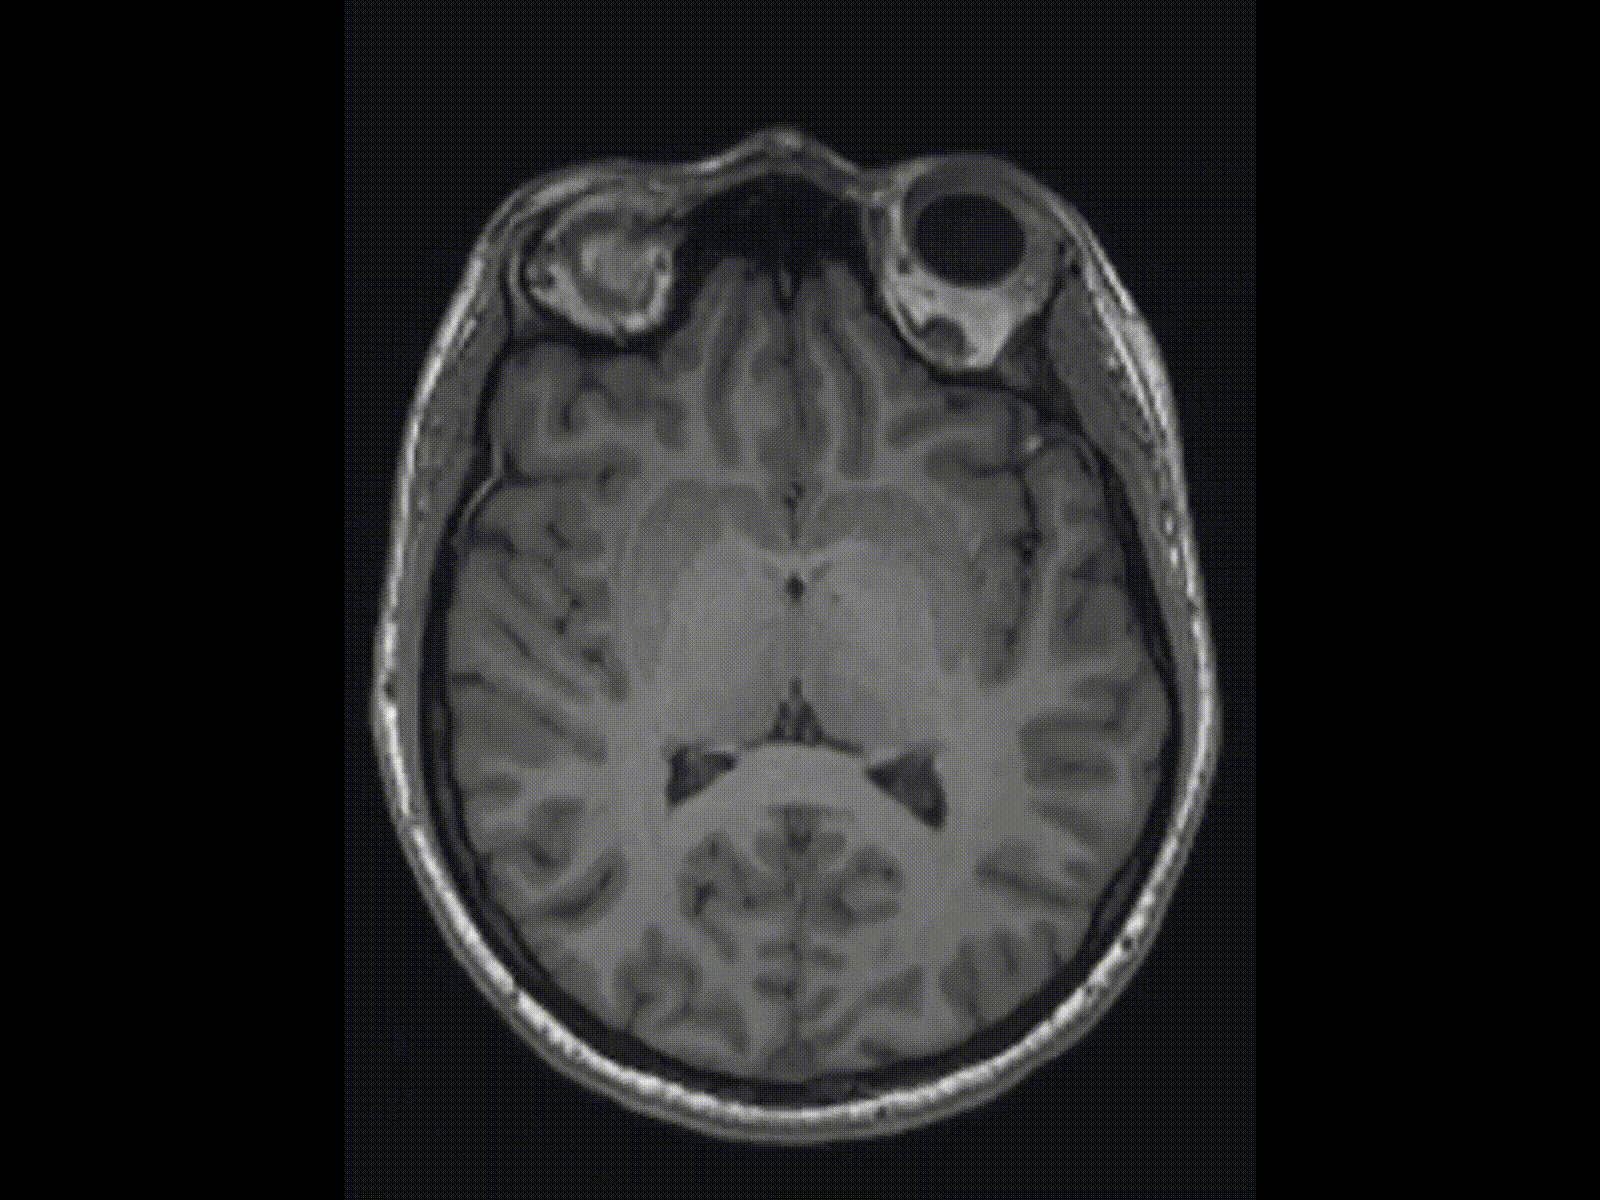

Ginsberg’s poem sends us hammering through outer space as if we enter Kubrick’s star gate in 2001: A Space Odyssey (1968). And why not? Our minds are as deep space as deep space itself. Neuroimaging slices away and couches forward momentum in Disney-style animation, but where are we going, and what does it mean?

Writers may think about brain activity more than normal people do. Writers may recognise the mind-universe better than others. I may wish for an atomic scale journey through my brain similar to Fantastic Voyage (1966), but neuroscience has not provided it yet. We have the Disney version already, but not the real thing.